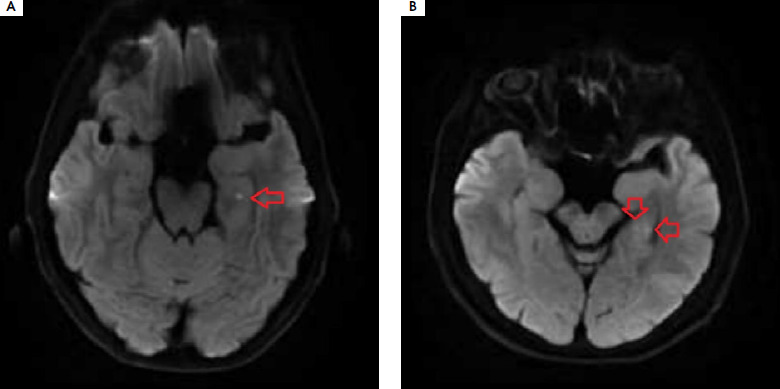

A 59-year-old patient was admitted to the Department of Neurology due to transient short-term memory disturbances lasting approximately 3.5 hours. The patient reported total amnesia of events during that period. The episode most likely occurred while riding a bicycle. The medical history revealed hypertension and migraine with aura. At admission, no abnormalities in neurological examination were noted. High blood pressure was recorded and activated partial thromboplastin time (aPTT) and prothrombin time (PT) were shortened (Table 1). The patient underwent extensive diagnostic evaluations to exclude hypercoagulable states (protein C, protein S, antithrombin III, D-dimers, fibrinogen were normal; no antiphospholipid antibodies were detected in serum nor mutations in the factor V Leiden and the prothrombin G20210A genes). A CT scan of the head and an angio-CT of cerebral vessels showed no significant pathologies. The electroencephalography was normal. Approximately 32 hours after the memory disturbances occurred, an MRI was performed, which revealed two small lesions in the DWI sequence within the left hippocampus. Based on Hodges and Warlow criteria, TGA was diagnosed. Controlled aPTT and PT performed after 4 weeks were normal. After 9 months, the patient was readmitted to the Department of Neurology due to persistent short-term memory disturbances lasting 4 hours. He did not remember what he had done in the last 24 hours. Neurological examination revealed no focal symptoms, he was asking the same questions every 30 seconds, being confused about time, but correctly oriented in terms of autopsychic awareness. High blood pressure values of 180/109 mmHg were noted again. Laboratory tests once again showed shortened aPTT and PT, which gradually normalized over the following days (Table 1). The patient was not taking any medications that affect blood clotting. The CT and MRI of the head, as well as video EEG, were normal. On the third day of hospitalization, an ambulatory blood pressure monitoring was performed, revealing exceeded blood pressure values during the day and at night; however, the highest recorded values were significantly lower than those at admission (Table 1). Clinical symptoms resolved within 24 hours, leaving an approximately 8-hour gap in memory. Another episode of TGA was diagnosed, and antihypertensive treatment was intensified.